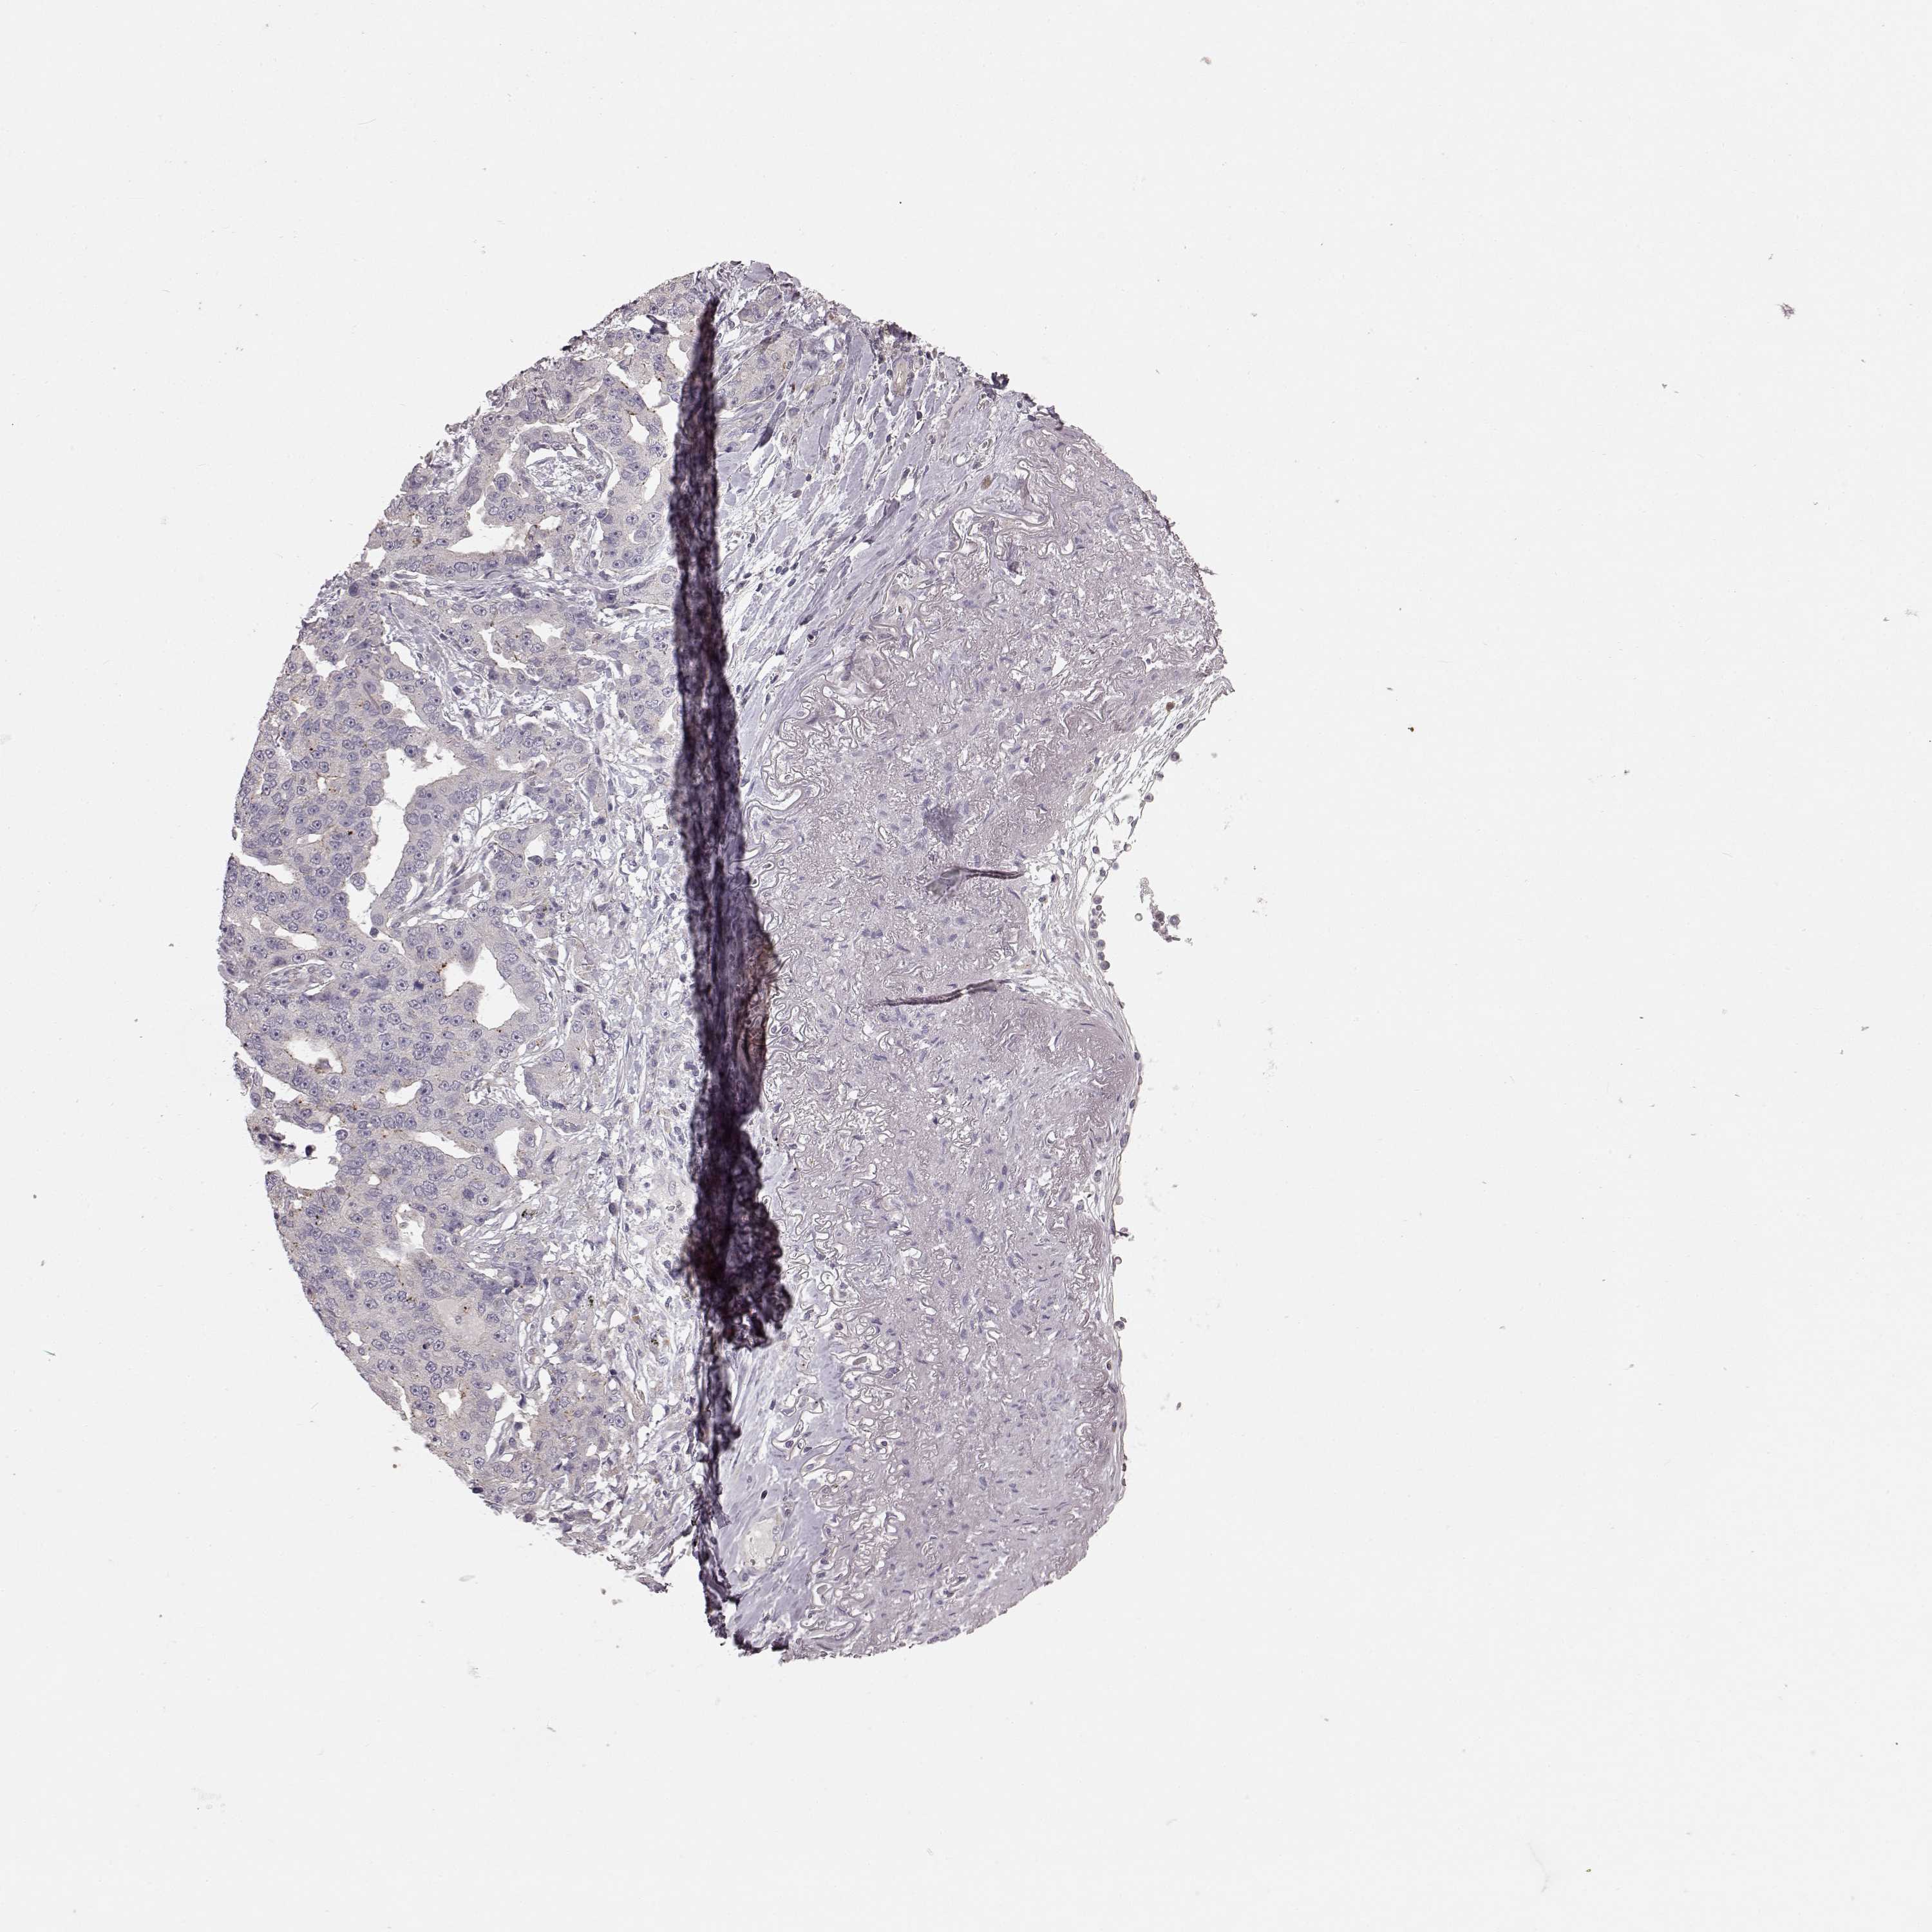

LUNG ADENOCARCINOMA (VALIDATION) - Interactive survival scatter ploti

The Survival Scatter plot shows the clinical status (i.e. dead or alive) for all individuals in the patient cohort, based on the same data that underlies the corresponding Kaplan-Meier plots. Patients that are alive at last time for follow-up are shown in blue and patients who have died during the study are shown in red.

The x-axis shows the expression levels (FPKM) of the investigated gene in the tumor tissue at the time of diagnosis. The y-axis shows the follow-up time after diagnosis (years). Both axes are complimented with kernel density curves demonstrating the data density over the axes. The top density plot shows the expression levels (FPKM) distribution among dead (red) and alive patients (blue). The right density plot shows the data density of the survived years of dead patients with high and low expression levels respectively, stratified using the cutoff indicated by the vertical dashed line through the Survival Scatter plot. This cutoff is automatically defined based on the FPKM cutoff that minimizes the p-score. The cutoff can be changed by dragging the vertical line or by entering a cutoff value in the square labeled "Current cut-off".

Under the Survival Scatter plot the p-score landscape (black curve; left axis) is shown together with dead median separation (red curve; right axis). Dead median separation is the difference in median mRNA expression between patients who have died with high and low expression, respectively. It is calculated as follows: median FPKM expression of dead patients with high expression - median FPKM expression of dead patients with low expression. This is intended to aid the user in visually exploring custom cutoffs and the associated p-scores and dead median separation.

Individual patient data is displayed and can be filtered by clicking on one or more of the category buttons on the top of the page. Categories describing expression level and patient information include: high, low, alive, dead, female, male and tumor stages. The scale of the x-axis can be toggled between linear and log-scale by clicking on the "x log" button. Mouse-over function shows TCGA ID, patient information and mRNA expression (FPKM) for each patient.

& Survival analysisi

Kaplan-Meier plots summarize results from analysis of correlation between mRNA expression level and patient survival. Patients were divided based on level of expression into one of the two groups "low" (under cut off) or "high" (over cut off). X-axis shows time for survival (years) and y-axis shows the probability of survival, where 1.0 corresponds to 100 percent.

SLC22A18 is not prognostic in Lung Adenocarcinoma (validation)

Best expression cut offi

Based on the FPKM value of each gene, patients were classified into two groups and association between prognosis (survival) and gene expression (FPKM) was examined. The best expression cut-off refers the FPKM value that yields maximal difference with regard to survival between the two groups at the lowest log-rank P-value. Best expression cut-off was selected based on survival analysis .

When clicking on this number, the vertical dashed line indicating cut-off, the interactive survival plot, and the Kaplan-Meier curve will be adjusted to show results based on the best expression cut-off.

: 3.92

P scorei

Log-rank P value for Kaplan-Meier plot showing results from analysis of correlation between mRNA expression level and patient survival.

N/A

TCGA RNA samplesi

RNA-seq data is reported as average FPKM (number Fragments Per Kilobase of exon per Million reads), generated by the The Cancer Genome Atlas (TCGA) .

Normal distribution across the dataset is visualized with box plots, shown as median and 25th and 75th percentiles. Points are displayed as outliers if they are above or below 1.5 times the interquartile range. FPKM values of the individual samples are presented next to the box plot.

Average pTPM 2.7

Number of samples 105